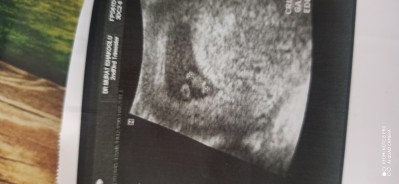

Tahmini cinsiyet sizce nedir

image

Gebelik haftası 7+1